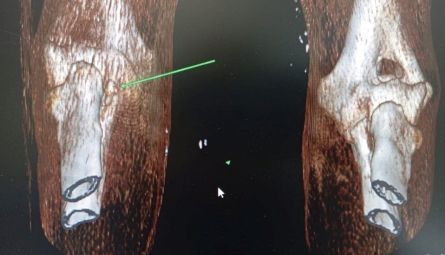

• КТ и МРТ. Оснащение ветеринарной больницы позволяет проводить диагностику плотных структур и комплексных систем организма с высокой детализацией.